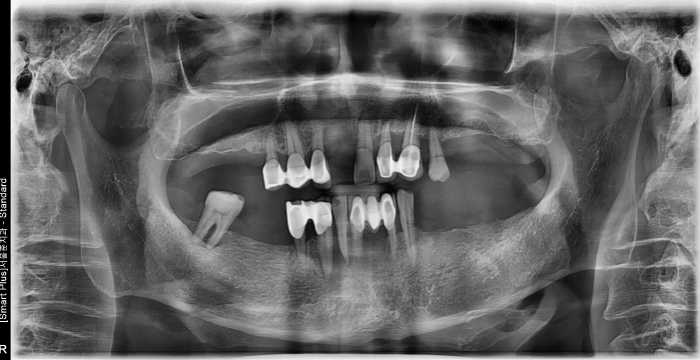

즉시 식립 임플란트 전후 사례

• 식립 전

식립 전